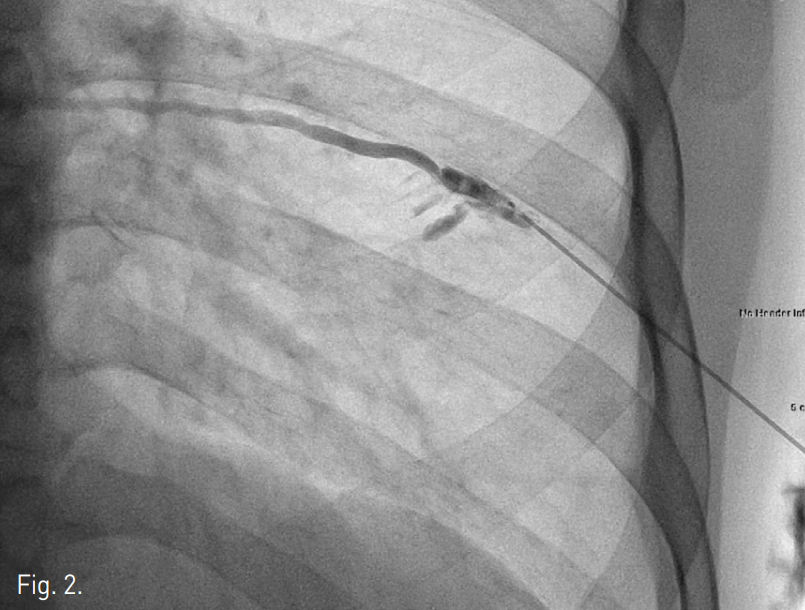

Prone position하에 22G 정맥주사용 바늘로 우측 외흉정맥 천자를 먼저 시도하였으나 조영제의 혈관 외 유출이 발생하여 실패하였음. 초음파 유도하에 우측 7번째 늑간정맥을 micropuncture needle (Cook, Bloomington, USA)로 천자하였고, 투시 유도하에 조영제를 주입하여 늑간정맥을 확인한 다음(Fig. 2) 0.018-inch hairy wire를 삽입하였음. Hairy wire를 거치한 상태에서 5F coaxial dilator를 통해 늑간정맥 조영술을 시행했을 때 기정맥을 통해 심장으로 조영제가 유입되었고(Fig. 3), hairy wire를 우심방까지 전진하였음. 늑간정맥 내로 삽입한 6F peel-away sheath내로 6F dual lumen PICC 카테터 (Vaxel, Navilyst Medical, USA)를 삽입하여 말단부가 우심방 내에 위치하도록 하고 시술을 마쳤음(Fig. 4).

Fig. 3

The venous blood flow draining into the heart via the azygos vein (arrows) and superior vena cava is clearly seen on the seventh intercostal venogram.